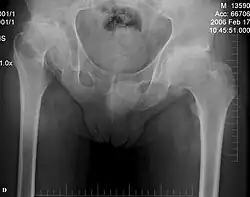

Patients with DMC require regular orthopedic follow-up to monitor and manage mobility difficulties and spinal abnormalities, particularly atlantoaxial instability, which can lead to spinal cord compression if untreated.[1][2] Procedures like spinal fusion or other stabilization methods are usually recommended if the cervical spine is affected, such as with hypoplasia in the odontoid process or partial cervical vertebral dislocation.[2][3] These are typically used to protect the cervical spinal cord and prevent weakness or paralysis.[3][7] Surgical interventions may be used to address other skeletal abnormalities, including shoulder and hip joint dislocations or subluxations.[1][2] In some cases, hip replacement surgery is necessary to manage severe hip degeneration.[3][7] Patients may also need orthopedic procedures such as early meniscectomy or posterior cervical spine fusion.[7]

For hip dysplasia, various treatment options and surgical procedures have been explored, including realignment of the proximal femur and/or acetabulum, realignment osteotomy, cheilectomy, and in more advanced cases, total hip replacement.[2][7] Studies suggest that osteotomies, including femoral and pelvic osteotomies, often fail to prevent the progression of hip subluxation and femoral head migration and may lead to progressive degeneration of the hip joint.[1][7]